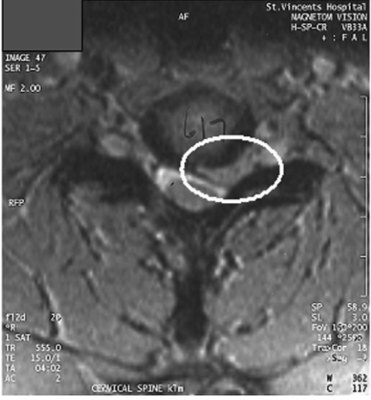

Bệnh nhân này đã được giới thiệu trở lại bác sĩ vì các triệu chứng không thuyên giảm sau ba buổi điều trị, kéo dài 2 tuần. Sau đó, bệnh nhân được giới thiệu đến một bác sĩ ngoại thần kinh, được chỉ định chụp MRI cho thấy thoát vị đĩa đệm lớn ở C6–7 (xem Hình ). Bác sĩ ngoại thần kinh đã kê thuốc prednisolone uống với liều 50 mg mỗi ngày trong 7 ngày, trong thời gian đó cánh tay được để yên. Kết quả ghi nhận có sự gia tăng sức mạnh ở cơ tam đầu trái và có phản xạ gân cơ tam đầu, mặc dù giảm đáng kể so với bên phải. Trong trường hợp này không cần can thiệp phẫu thuật. Phẫu thuật có thể được chỉ định nếu có khiếm khuyết vận động tiến triển, ảnh hưởng đến chức năng hoặc nếu đau kéo dài hơn 6-12 tuần (Carette & Fehlings 2005).

Hình ảnh MRI cột sống cổ C6-7 cho thấy thoát vị lệch trái.